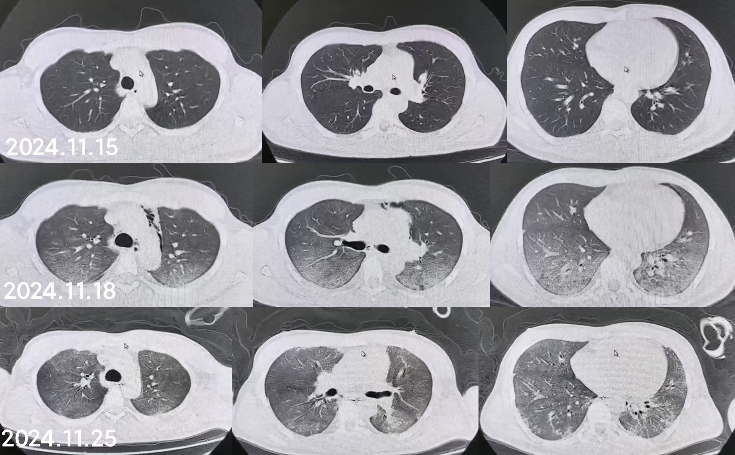

同时给予镇痛、镇静联合肌松,去甲肾上腺素泵入维持血压,俯卧位通气,B某入院后出现高热,经验性给予美罗培南联合万古霉素抗感染治疗,后降阶梯调整为哌拉西林他唑巴坦联合万古霉素治疗;C某抗感染方案为经验性使用万古霉素联合哌拉西林他唑巴坦治疗,痰培养出鲍曼不动杆菌后改为替加环素、头孢哌酮舒巴坦及万古霉素治疗;根据《刺激性气体中毒诊治专家共识》[5]中关于重症患者的治疗措施,同时给予2人泮托拉唑抑酸护胃,氨溴索、富露施化痰、甲泼尼龙抗炎、西维来司他纳及乌司他丁清除炎性介质,维生素C抗氧化、保肝、输血补液,纤支镜吸痰及肺泡灌洗,维持水电解质平衡及营养支持治疗,特别考虑到肺损伤情况,在使用有创通气时给予超保护性通气策略[5, 7];2人仍先后出现气胸、纵膈气肿,行胸腔闭式引流;持续V-V ECMO治疗15 d后,肺部纤维化不可逆转,高分辨率CT肺纤维化评分 > 75%(图 3、4),符合终末期肺病标准,有肺移植指征[8],经评估后2人顺利完成病变肺组织切除(图 5),双侧序贯肺移植,术后患者复查胸片肺部恢复正常(图 6),2位患者术后气管切管接呼吸机辅助通气,并给予泼尼松、他克莫司、吗替麦考酚酯抗排异治疗,其余根据病情给予万古霉素调节肠道菌群、抗感染、保肝、抗凝、呼吸康复锻炼等治疗,后顺利脱机、拔除气切套管,病情稳定出院,后续规律复查胸部CT(图 7)恢复良好。

| 图 3 B某发病15 d时胸部CT表现 |

| 图 4 C某发病15 d时胸部CT表现 |

急性吸入性有机氟中毒常见于工业生产及废液处理中发生意外损伤,导致在短时间内吸入过量有机氟单体裂解气、残液气或热解气等所致的以呼吸系统损害为主的全身性损伤。急性肺损伤是其主要的病理生理学变化[9],其核心病理生理学基础是氧化应激及其介导的剧烈炎症级联反应[7],毒物吸入后,首先直接损伤肺泡上皮和毛细血管内皮细胞,导致血管通透性急剧增高[10],减少肺表面活性物质,造成肺与肺间质水肿、透明膜形成,这解释了本组患者早期均出现两肺弥漫性渗出的影像学表现。随后,活化的中性粒细胞和巨噬细胞释放大量氧自由基及蛋白酶,进一步破坏肺实质结构,形成肺泡隔增生致肺纤维化[11-12],并形成恶性循环。这即导致通气不足、弥散障碍、肺内分流增加和通气/血流比失衡,肺泡塌陷、细支气管闭塞、肺不张,最终导致ARDS,这一机制与本组病例中出现的呼吸困难及难以纠正的低氧血症和高碳酸血症(即ARDS)相符合。

更主要的是,上述氧化应激与炎症反应是驱动肺组织不可逆纤维化的重要始动因素。在毒性损伤的持续刺激下,上皮-间质转化过程被异常激活[5, 13],肺泡上皮细胞转化为成纤维细胞,导致成纤维细胞增生及细胞外基质过度沉积[13]。因此在中毒后短期内即出现暴发性、不可逆的肺纤维化[14]。其直接临床后果是肺顺应性严重丧失,肺组织脆性显著增加。这正是在救治过程中,即便本团队应用了超保护性通气策略严格控制潮气量、平台压及驱动压,两例重症患者仍不可避免地发生了气胸和纵隔气肿的根本原因。此时,机械通气本身已成为气压伤的风险来源[6],凸显了毒性肺损伤的极端严重性。